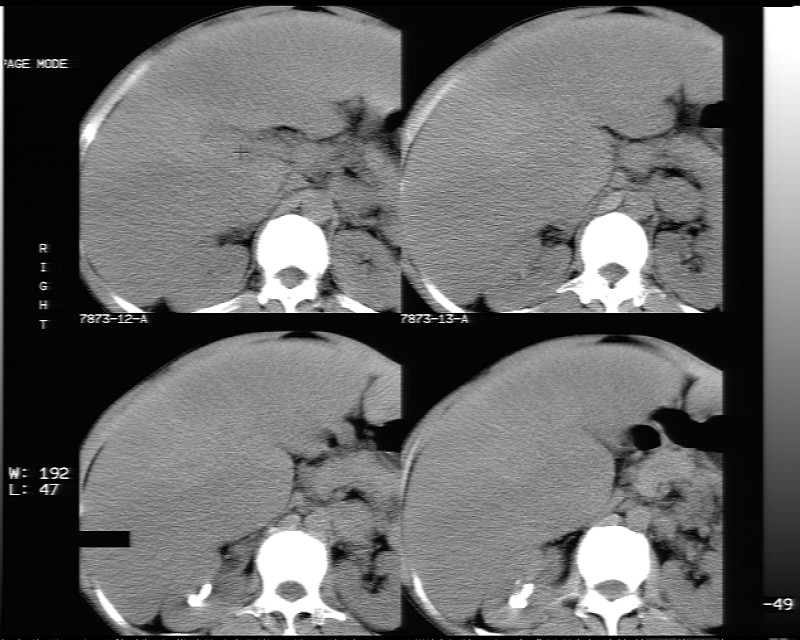

平扫示:

脂肪肝。

局灶性脂肪肝

支持局灶性脂肪肝

脂肪肝

我想也是脂肪肝。

不均匀性脂肪肝

不均匀性脂肪肝 。支持!

非均质性脂肪肝。

不均匀性脂肪肝。

支持脂肪肝【无占位性,高低密度区同期强化,平扫与强化的密度成比例】

不均匀性脂肪肝。肝脏体积稍大,不除外合并肝功能损害。

1、不均匀脂肪肝;2、布加氏综合症(肝脏肿大,门脉纤细,下腔海绵状变性,肠系膜上静脉显著扩张)。